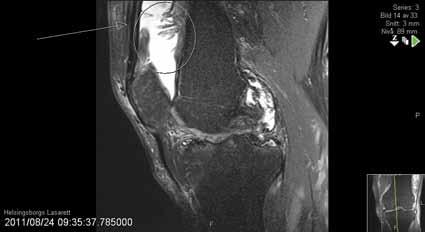

Fråga 2012-6 5p

Kvinna 57 årig tidigare frisk kvinna som inte tidigare har haft några problem med sina knäleder. En dag under vårens trädgårdsarbete känt smärtor i vänster knäled. Söker efter några dagar som jourfall då smärtorna snarast tenderar att öka. I status finner du lätt hydrops. Lätt rörelseinskränkning vänster jämfört med höger knäled. Lätt till måttlig ömhet medialt. Normal SR och CRP.

a. Differentialdiagnoser? (1p)

b. Hur handlägger Du patienten vid detta besök? (2p)

c. Hur utreder man ytterligare om patienten återkommer pga tilltagande besvär efter ett par veckor? (2p)

a. Troliga diagnoser är degenerativ meniskruptur/artros, spontan knäledsosteonekros eller insufficiensfraktur.

b. Noggrant knä- och höftstatus eventuellt slätröntgen och patientinformation om möjliga diagnoser. Smärtlindring och aktivitetsråd.

c. Vidare utredning med MR kan vara

indicerad speciellt för att kartlägga en eventuell osteonekros. Tc-scintigrafi kan också leda till rätt diagnos.